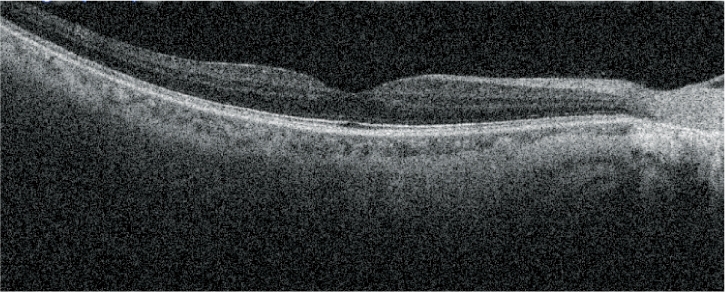

視網膜分析

OCT靈敏度可選

根據病歷,通過選擇適宜的OCT靈敏度,以確保對介質渾濁患者的圖像采集。